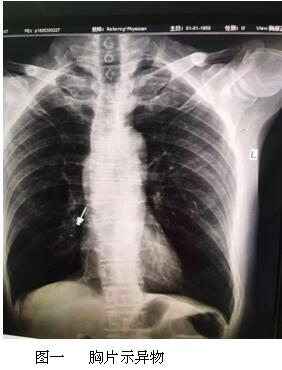

六月最后一天的上午,內(nèi)鏡中心來(lái)了一名特殊的患者,患者表情焦慮,訴于外院補(bǔ)牙時(shí),不小心把補(bǔ)牙的一顆螺絲吞下,現(xiàn)咽喉部明顯不適,于我院耳鼻喉行喉鏡檢查,未見(jiàn)明顯異物,內(nèi)鏡中心伍友興主任聽(tīng)聞后,考慮異物可能卡在食管上段,持鏡給予患者行胃鏡檢查,但是反復(fù)觀察食道、胃及十二指腸,并未找到患者所描述的異物。是不是有可能異物已經(jīng)掉入十二指腸以下的消化道了呢?如果已經(jīng)掉入小腸,這一顆大約長(zhǎng)2cm的螺絲,表面無(wú)明顯銳利邊緣,刺破腸管的可能性較小,可自行隨大便排出,正當(dāng)我們準(zhǔn)備松一口氣告訴患者胃鏡下未見(jiàn)明顯異物時(shí),患者輕輕的咳嗽兩聲引起了伍主任的注意,“快去行胸部照片,異物可能掉入氣管”伍主任說(shuō)到,患者遂行胸部照片,見(jiàn)異物果然出現(xiàn)在患者右側(cè)的肺里,為進(jìn)一步確定異物部位,給予行胸部CT檢查,并積極聯(lián)系呼吸內(nèi)科豐偉民主任,黃雪英老師與豐主任兩人密切配合,在支氣管鏡下看到右側(cè)支氣管下段,找到了讓人揪心的異物,順利取出,此刻患者緊縮的眉頭終于舒展開(kāi)來(lái),連連向我們醫(yī)務(wù)人員道謝。